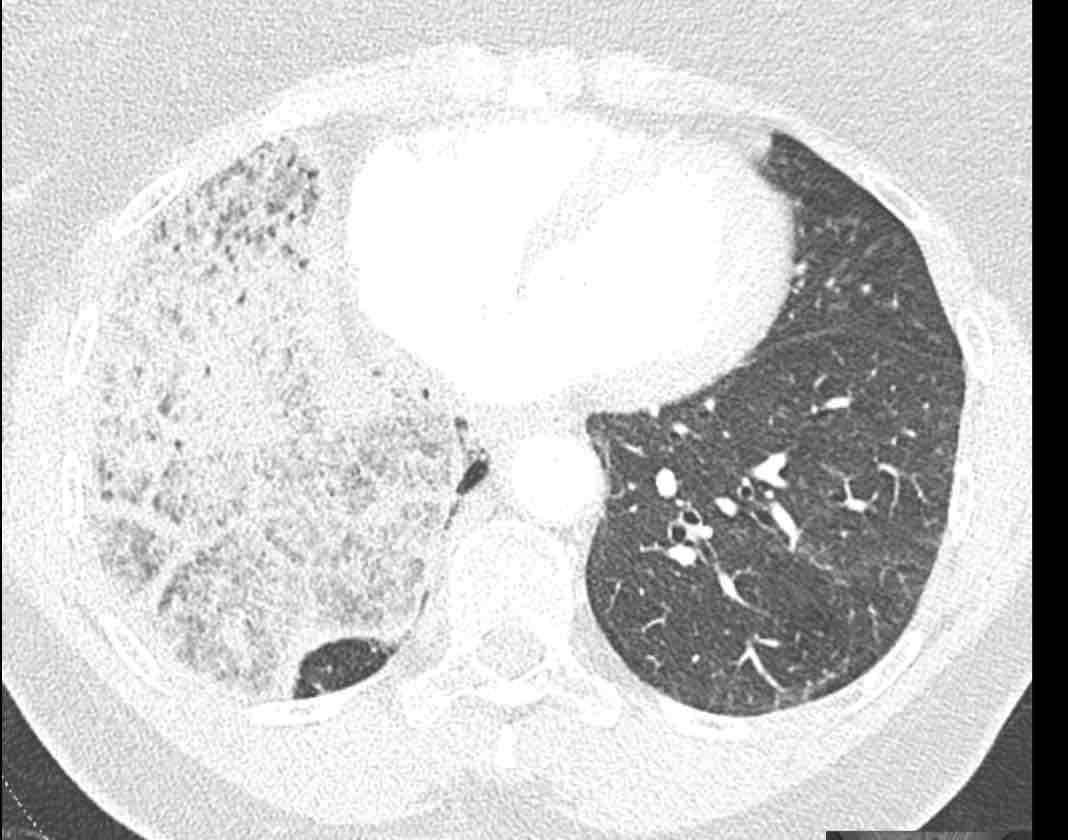

Các hình ảnh này của một bệnh nhân nữ 65 tuổi sau khi đã cắt thùy trên phổi phải trước đó.

Trước tiên, hãy cuộn qua các hình ảnh.

Hình ảnh

Theo dõi lần lượt các phế quản giúp xác định mỏm cắt thùy trên phổi phải (RUL), phế quản thùy giữa bị tắc nghẽn và các phế quản thùy dưới còn thông.

Điều này xác định mô phổi bị di lệch xuống dưới chính là thùy giữa phổi phải (RML), thấy rõ nhất trên mặt phẳng đứng dọc.

Thùy giữa phổi phải bị phù nề và không còn được tưới máu.

Ngoài ra còn thấy hình ảnh ứ máu và xẹp phổi ở các phân thùy đáy của thùy dưới phổi phải (RLL), hiện nằm phía trên thùy giữa phổi phải đã bị nhồi máu.